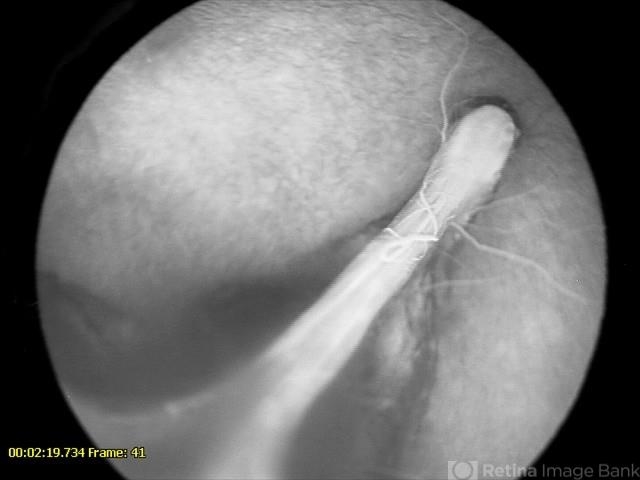

- Late phase angiogram of 10-month-old male with congenital retinal fold. Contralateral eye had normal angiography.